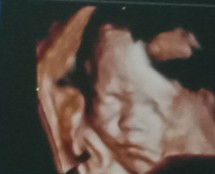

HB datar rendah

Baru2 ni doc naikkn pengmbilan zincofer sy kpd 2 biji sehari.. hb sy datar 10.2- 10.3... sape2 ambik ubat ni msti tau derita nk mnum ubat zincofer.. btw sy xpenah skip pon ambik ubat ni cuma nk ikhtiar lg. Sy dh mkn mcm2 dh yg bole naikkn hb tpi xberkesan naik. belek2 kt fb ada nmpk iklan jus mamariam kata elok utk naikkn hb dgn cepat. Ada x sape2 yg ada pngalaman ambil jus mamariam ni? Bole sharekn.. nk tau gak berkesan ke tak #firstbaby